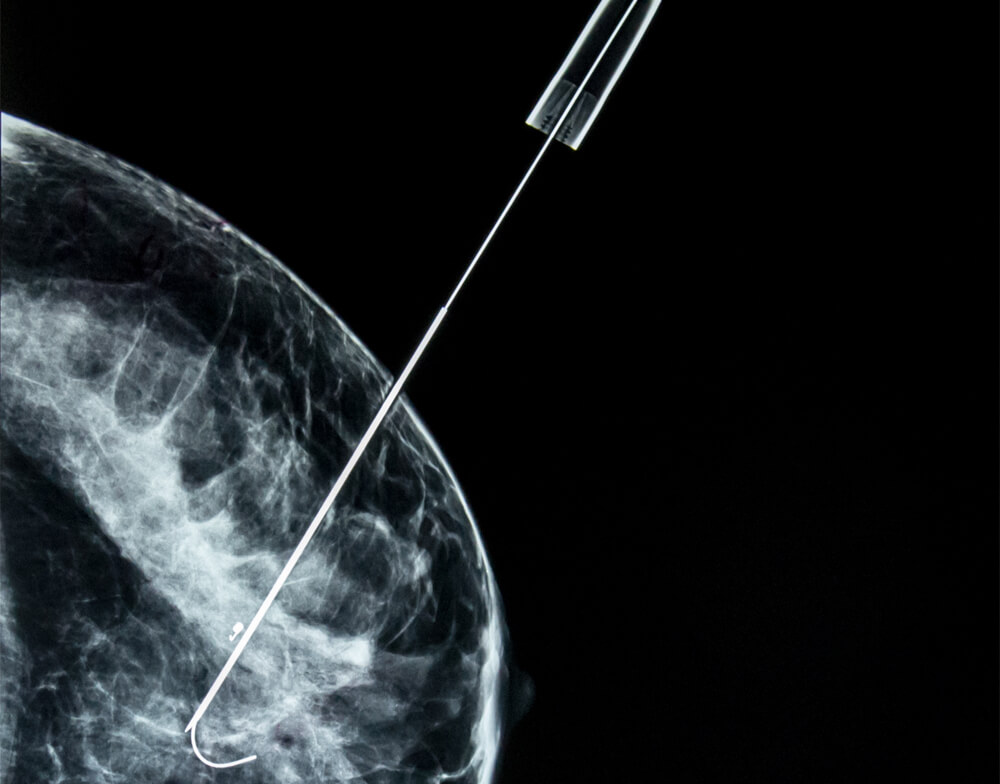

Ο ευρύτερα διαδεδομένος είναι ο εντοπισμός με ειδικό συρμάτινο οδηγό (hook wire).

Εισάγεται στο μαστό μια λεπτή βελόνη η οποία κατευθύνεται προς τη βλάβη-στόχο. Αφού διαπεράσει τη βλάβη, η βελόνη αποσύρεται και απελευθερώνει τον συρμάτινο οδηγό.

Ο οδηγός έχει άκρο σαν άγκυρα και «αγκυρώνει» σταθερά στη βλάβη. Στο χειρουργείο ακολουθούμε τον οδηγό και εντοπίζουμε τη βλάβη.